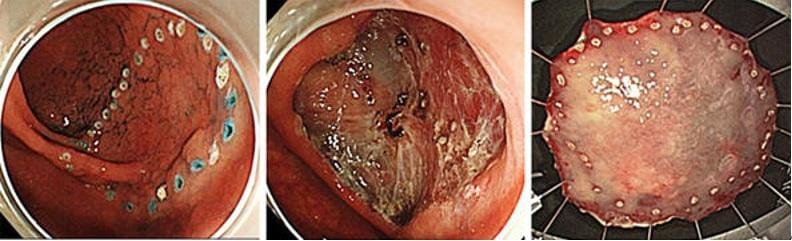

内視鏡的粘膜下層剥離術(ESD)

ESDは病変を分割することなく一括で切除するために開発された治療法です。専用のナイフを用いて病変の端から少しずつ確実に剥離して大きな病変でも最終的に一括切除します。一括切除することで治療後の正確な病理(顕微鏡検査)評価が可能となり、癌が取りきれたか、どこまで深く浸潤しているかなどを判定し再発リスクや追加治療の必要性が適切に判断出来ます。再発リスクがあるような深めの癌を疑う場合は治療前に超音波内視鏡検査(細径プロープ)も追加し、より正確な診断を心掛けております。

早期胃癌に対するESD治療

早期大腸癌に対するESD治療